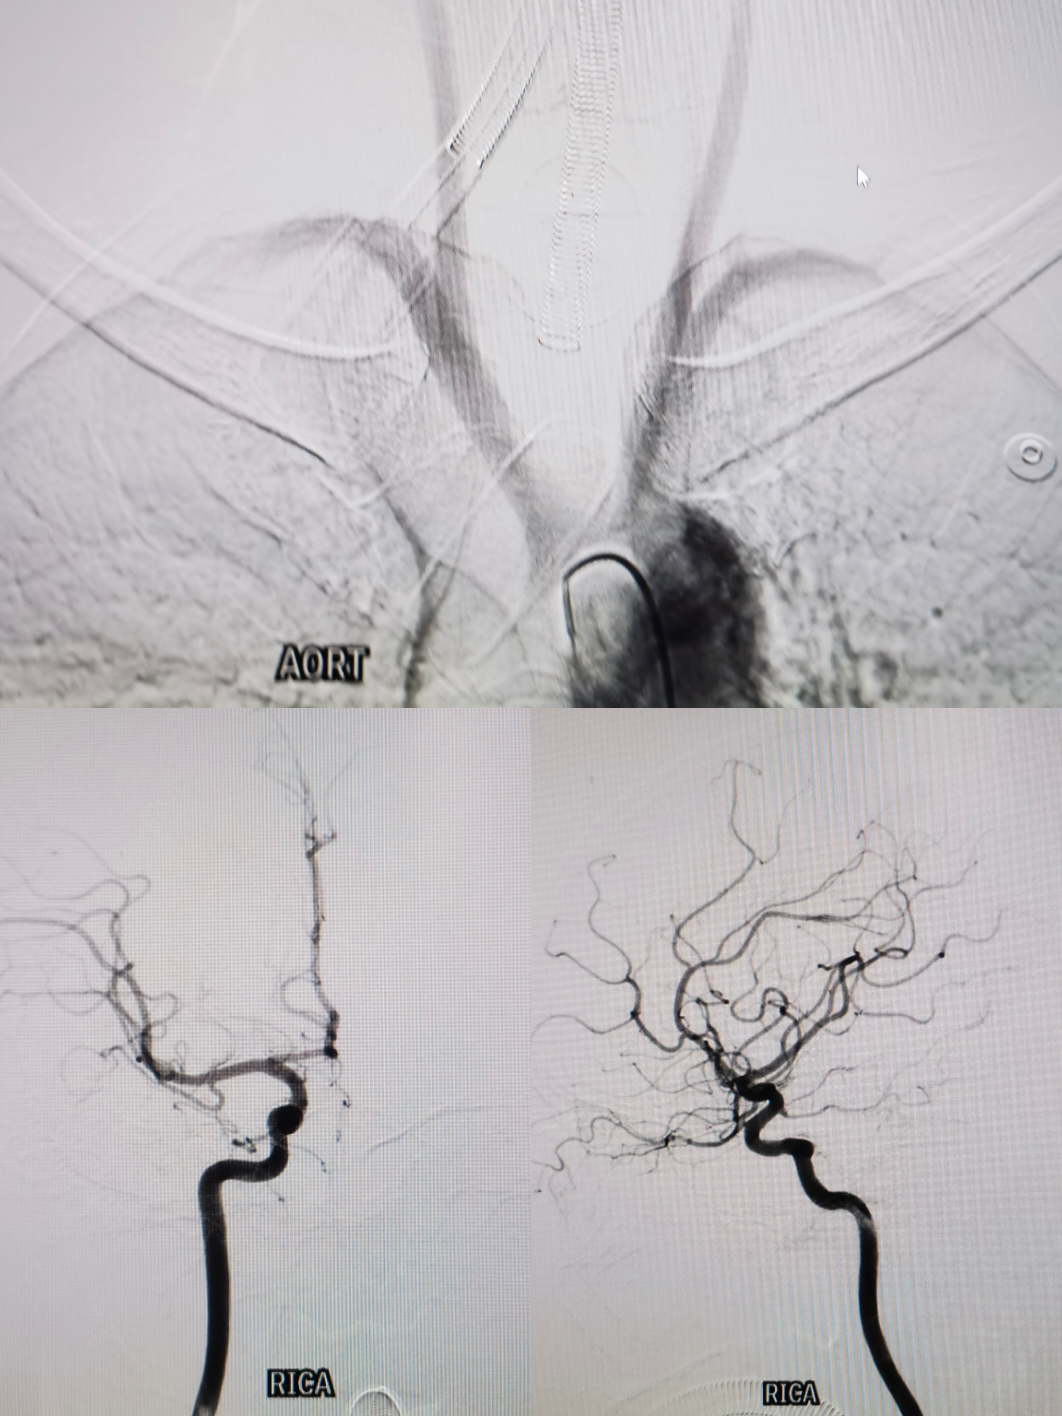

主动脉弓1型弓,右侧颈内:右侧大脑前A1存在

双椎造影无特殊

左侧颈内造影:前交通动脉瘤,窄颈